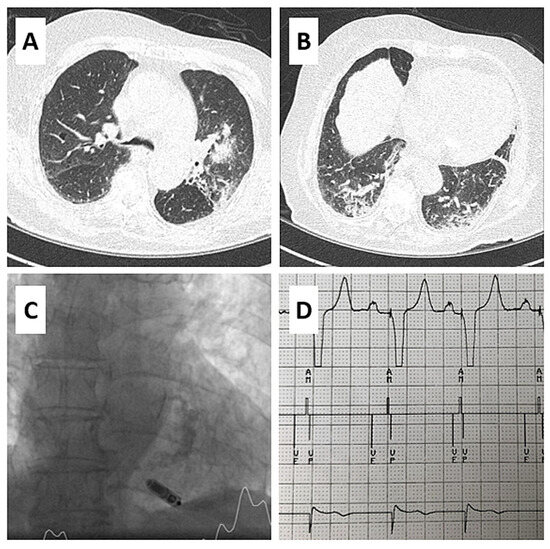

AV Synchronous Pacing with a Single-Chamber Leadless Pacemaker in a Patient with COVID-19 and Complete AV Block

by Özkartal Tardu, Demarchi Andrea, Conte Giulio, Araco Marco and Auricchio Angelo

Cardiovasc. Med. 2022, 25(3), 1; https://doi.org/10.4414/cvm.2021.02262 - 1 May 2021

We present the first case of implantation of a novel singlechamber leadless pacemaker capable of atrioventricular (AV) synchronous pacing in a patient with COVID-19 and complete AV block. This device not only promotes AV synchrony, but also eliminates risk of iatrogenic pneumothorax and [...] Read more.

We present the first case of implantation of a novel singlechamber leadless pacemaker capable of atrioventricular (AV) synchronous pacing in a patient with COVID-19 and complete AV block. This device not only promotes AV synchrony, but also eliminates risk of iatrogenic pneumothorax and pocket complications, such as haematoma and infection and may therefore be considered a valuable alternative to a dual-chamber pacemaker. Full article